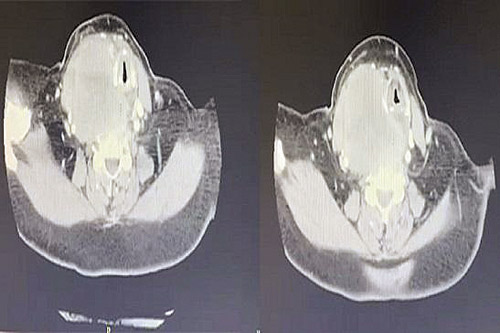

وقال د. طلال الجهني استشاري جراحة الأنف والأذن والحنجرة وأورام الرأس والرقبة، أن المريضة وهي في العقد السادس من العمر راجعت العيادة، وهي تعاني من أعراض حادة، تتمثل في صعوبة بالغة في التنفس والبلع والكلام، وأخضعت على الفور إلى فحوصات طبية دقيقة أبرزها الأشعة المقطعية، كشفت النتائج وجود الورم الذي كان ضاغطاً بشدة على الأوردة والشرايين الرئيسية في الرقبة والحنجرة والقصبة الهوائية والمريء، ما سبب تلك الأعراض الحادة.